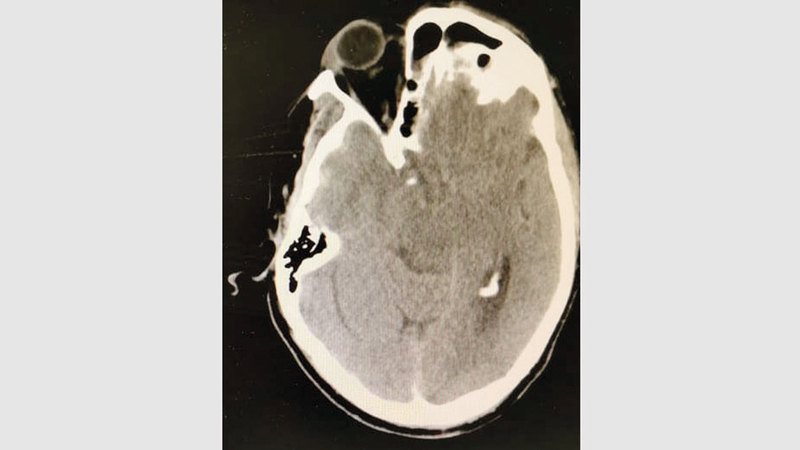

صورة الدماغ.

وذكر استشاري جراحة المخ والأعصاب والعمود الفقري في مستشفى برايم بدبي، الدكتور ثائر درويش، أن المريض، وهو من جنسية آسيوية، ويبلغ 68 عاماً، تعرض لحادثة سقوط مدوٍّ على الرأس، أثناء استحمامه في منزله، ما تسبب له في حدوث فتق وتهشم في الدماغ، وأدى إلى حدوث نزيف حاد، ودخوله في غيبوبة كاملة.

وأكد التعامل معه كحالة حرجة، وإدخاله إلى غرفة العمليات فوراً، لإزالة الدماء عن الدماغ، وتخفيف الضغط عنه، الأمر الذي أنقذ حياته.